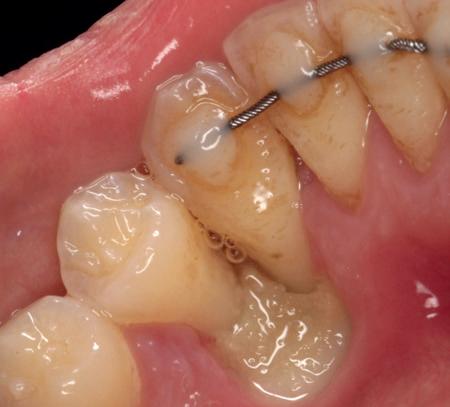

Er wordt besloten om botmateriaal te plaatsen in de extractie-alveole. Vervolgens wordt het afgesloten met een titanium versterkt d-PTFE membraan (afbeelding 2). Na vier weken wordt het membraan verwijderd.

Zes maanden na extractie wordt het implantaat 37 geplaatst. Er is sprake van een goede genezing en de processushoogte en -breedte zijn behouden en opgebouwd. Ook is er zichtbaar gekeratiniseerd weefsel

gewonnen. De wond kan na het plaatsen van een healing abutment primair gesloten worden (Afbeelding 3a-3d).

In afbeeldingen 4a-c is het resultaat drie maanden na het plaatsen van het implantaat te zien. De genezing is volledig en de verwijzer kan de suprastructuur vervaardigen (afbeelding 4a-4c).